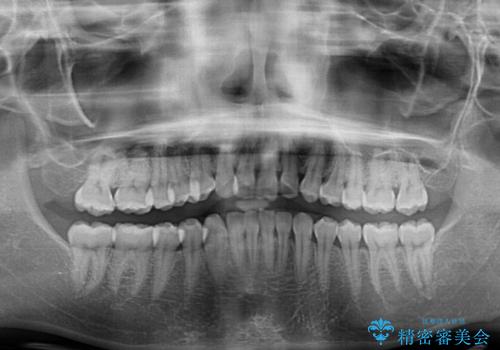

- 上下前歯のデコボコを気にして来院された患者様です。

全体的に叢生は軽度であったため、インビザラインにて矯正治療を行うこととしました。

舌の突出癖改善がうまくいかず、途中で舌小帯の切除を行いました。

気になる段差を納得いくまで改善させたため、治療期間は長くなりましたが、綺麗な仕上がりとなりました。